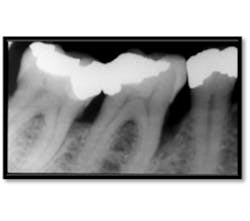

Initial perio charting (above left), Pretreatment radiograph (above right)

As you can see, calculus is visible on the mesial surfaces of both molars and the extent of bone loss mesial of # 30 is significant. 18 months post treatment: